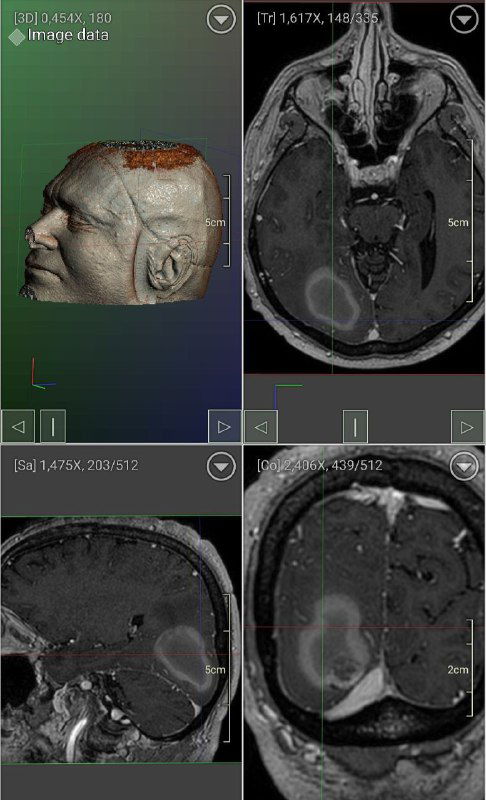

Глиобластома часто протекает скрыто и может достигать больших размеров; на снимках — опухоль, заполняющая более половины правого полушария.